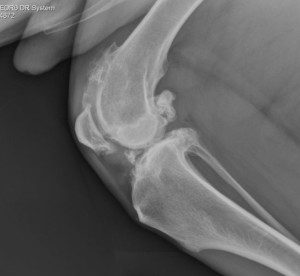

Total joint replacement of any joint carries the risks of possible complications. Therefore, total knee replacement is reserved for dogs with painful knee conditions, where either conventional surgical techniques have not been successful or where diseased joints are unresponsive to conservative management using pain relief and rehabilitation. The most common cause of knee pain is osteoarthritis secondary to cruciate disease, trauma or malformation of the knee. Examples of severe osteoarthritis are shown below:

Lucy is a 10-year-old golden retriever who was referred with significant pain and lameness affecting her left hind limb, attributed to considerable arthrosis of the knee. A CT scan revealed collapse of the medial compartment (one half of the knee) with bone-on-bone wear and complete erosion of the caudo-medial tibial plateau (parts of the tibia articular surface). In Lucy’s case, the cruciate and collateral ligaments were disrupted. Therefore, a custom rotating-hinge total knee replacement was designed and manufactured for her. The two components had one metal stem each that were anchored into the femur and tibia using cement, while hydroxyapatite cover on metal surfaces that had direct contact with bone helped with bone on-growth.